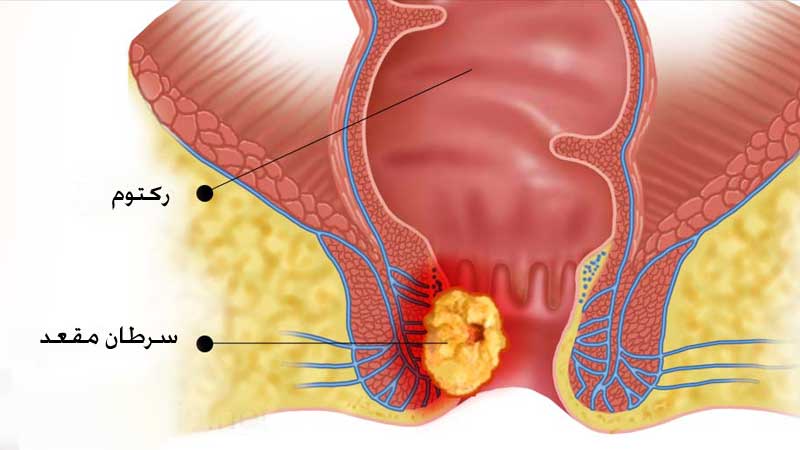

آیا همیشه باید زگیلها برداشته شوند؟

بله. اگر زگیل مقعدی برداشته نشود، معمولاً بزرگتر شده و تکثیر میگردند. در صورت عدم درمان، زگیل تناسلی مقعدی ممکن است منجر به افزایش خطر ابتلا به سرطان مقعد در ناحیه آسیب دیده شوند. خوشبختانه، خطر ابتلا به سرطان مقعد بسیار نادر است.

دیسپلازی مقعدی چیست؟

زگیلها پس از برداشته شدن برای بررسی به پاتولوژی فرستاده میشوند. برخی از زگیلها در زیر میکروسکوپ دچار تغییرات غیرطبیعی میباشند. به این تغییرات دیسپلازی مقعدی گفته میشود و با میکروسکوپ میتوان پیشرفت دیسپلازی یا تغییرات غیر طبیعی آنها را تعیین کرد. این تغییرات توسط پزشکان به نئوپلازی داخل اپیتلیومی با درجه بالا و درجه پایین تقسیم میشوند.

به سلول هایی که بدخیم یا پیش بدخیم میشوند، اما به عمق پوست حمله نمیکنند، نئوپلازی با درجه بالا گفته میشود. اگرچه این بیماری به احتمال زیاد پیشرونده به سرطان مقعد است، اما این سرطان مقعد نیست و متفاوت از سرطان مقعد درمان میشود.

چرا باید دیسپلازی مقعدی را درمان کنیم؟

هنگامی که دیسپلازی مقعد داشته باشید، بندرت خود به خود از بین میرود. اگرچه هنوز هم بسیار نادر است، اما خطر ابتلا به سرطان مقعد در بیماران با سابقه دیسپلازی مقعد (کمتر از 5%) کمی وجود دارد. به نظر میرسد پیشرفت آن در بیماران مبتلا به HIV مثبت بیشتر است. خطر پیشرفت به سرطان مقعد ممکن است در بین بیماران مبتلا به HIV مثبت 50 تا 10٪ متغیر باشد.

علیرغم برداشت گسترده بافت خطر عود هم چنان وجود دارد و هم چنین خطر ایجاد عوارضی مانند تنگی مقعد(باریک شدن ناحیه) و بی اختیاری مدفوع بسیار زیاد است. تخریب هدفمند با روش آنوسکوپی با وضوح بالا برای شناسایی، بیوپسی و از بین بردن دیسپلازی مقعدی بدون زمان بهبود طولانی مدت و عوارض مرتبط بسیار مؤثر است. با این وجود، هنوز خطر عود در این روش 80- 20٪ گزارش شده است. عوارض جراحی مانند بی اختیاری و تنگی مقعد به طور کلی در این روش دیده نمیشود. خوشبختانه، هر دو روش از پیشرفت دیسپلازی مقعدی به سرطان مقعد جلوگیری میکنند.